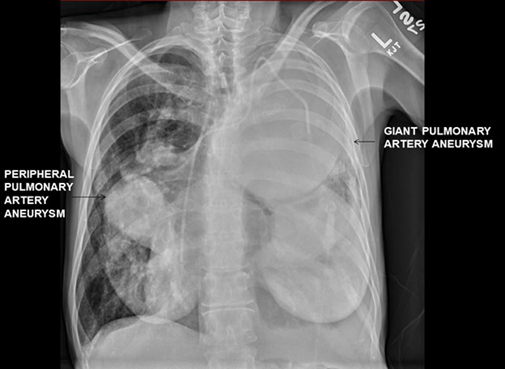

Las imágenes aquí incluidas demuestran aneurismas gigantes de la arteria pulmonar en un paciente con hipertensión arterial pulmonar idiopática (Imagen 1). Además de la arteria pulmonar principal, hay aneurismas también en las arterias pulmonares izquierda y derecha, los cuales comprimen el parénquima pulmonar (Imagen 2).

IMAGEN 1 Aneurismas gigantes de la arteria pulmonar en un paciente con hipertensión arterial pulmonar idiopática.

IMAGEN 2 Aneurismas en las arterias pulmonares izquierda y derecha, los cuales comprimen el parénquima pulmonar.

La cardiopatía congénita, la infección y la hipertensión arterial pulmonar son causas preponderantes de aneurismas de la arteria pulmonar. Los aneurismas gigantes (diámetro >8 centímetros) pueden comprimir las estructuras adyacentes, incluido el árbol traqueobronquial, generando disnea, tos, dolor precordial, sibilancia y estridor. La hemoptisis puede anunciar la ruptura de un aneurisma. Además, la obstrucción dinámica del flujo de aire puede generar traquebroncomalacia 1,2.

El diagnóstico suele ser radiológico. La discordancia entre ventilación y perfusión a causa del colapso pulmonar en pacientes con aneurismas gigantes puede empeorar la cianosis y la hipoxemia relacionadas con hipertensión arterial pulmonar preexistente. A fin de aliviar tanto el colapso como la compresión traqueobronquial puede ser necesario recurrir a una endoprótesis de vía aérea.